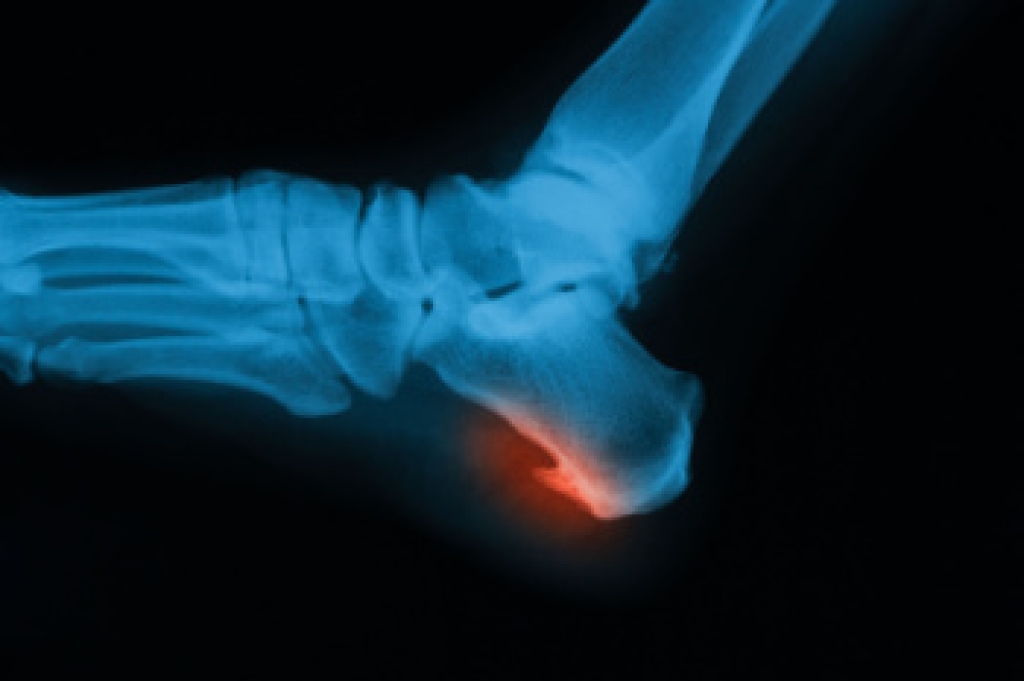

Heel pain in older adults often stems from age-related changes in the feet, including soft tissue degeneration, reduced bone density, and long-standing biomechanical stress. A frequent cause is plantar fasciitis, an inflammatory condition of the plantar fascia that commonly produces sharp pain with the first steps after rest. Heel spurs may develop beneath the calcaneus, or heel bone, and can contribute to additional discomfort. Achilles tendinitis may cause pain at the back of the heel due to overuse or limited flexibility, while arthritis in the rearfoot or midfoot joints can create stiffness and reduced mobility. Seniors are also at increased risk for calcaneal stress fractures, retrocalcaneal bursitis, and heel pad atrophy, which results from thinning of the natural cushioning under the heel. Nerve conditions such as tarsal tunnel syndrome or peripheral neuropathy may cause burning or tingling heel pain. If you have ongoing heel pain, it is suggested that you make an appointment with a podiatrist to determine the underlying cause and select appropriate treatment.

Heel spurs are another cause of pain. When the tissues of the plantar fascia undergo a great deal of stress, it can lead to ligament separation from the heel bone, causing heel spurs.